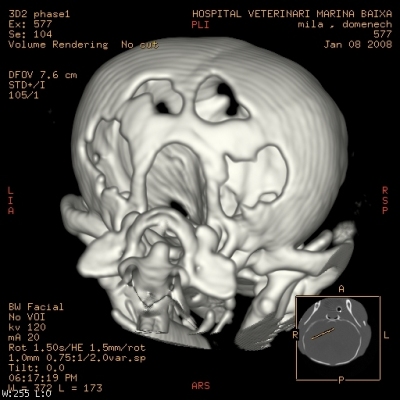

Cerebro y cráneo:

Maxilofacial: